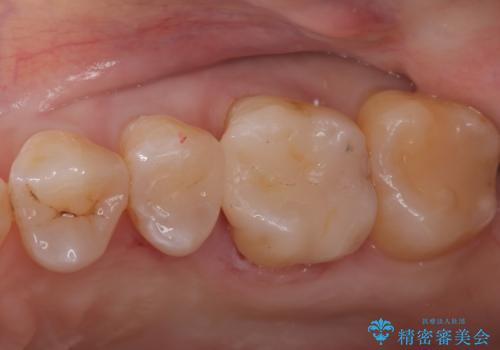

- 左上5番と6番の奥歯に入っている金属の詰め物(メタルインレー)の見た目を改善したいという主訴でご来院されました。お口の中の金属をなくしたいという患者様のご希望を踏まえ、天然歯に近い色と質感を持つセラミックインレーに交換する治療計画を立案。これにより、見た目の改善だけでなく、金属アレルギーのリスクを排除したメタルフリーの環境を実現することを目指しました。

治療では、まず古い金属のインレーを慎重に取り外しました。金属の下に隠れていた虫歯の再発がないかを確認し、歯を丁寧に形成。その後、精密な型取りから患者様の歯の色に合わせたオーダーメイドのセラミックインレーを作製しました。セラミックは、自然な光の透過性を持つため、周囲の歯と区別がつかないほどの美しい仕上がりとなります。適合性の高いセラミックインレーを装着することで、再発のリスクを抑えつつ、長年のコンプレックスだった銀歯がなくなり、笑顔でも気にならない自然な奥歯を取り戻していただけました。